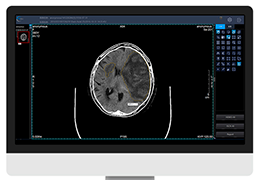

ANYTHINK 经导管主动脉瓣膜置换术分析系统